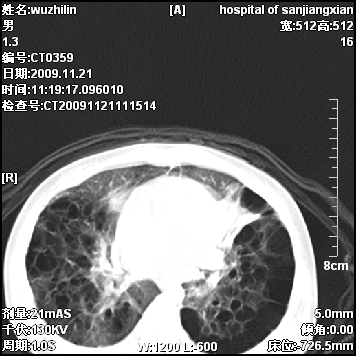

弥漫性薄壁囊腔,胸膜下及肺底部占优势,双上肺磨玻璃密度影,首先考虑特发性肺间质纤维化,其次囊性肺纤维化,肺淋巴管平滑肌瘤病嗜酸性肉芽肿等;要结合临床综合考虑。

两肺布满多个薄壁含气囊腔,以下肺居多,伴磨玻璃样密度影,左侧气胸。两肺发育不全、两肺多发肺囊肿并感染,其次考虑肺囊腺瘤。